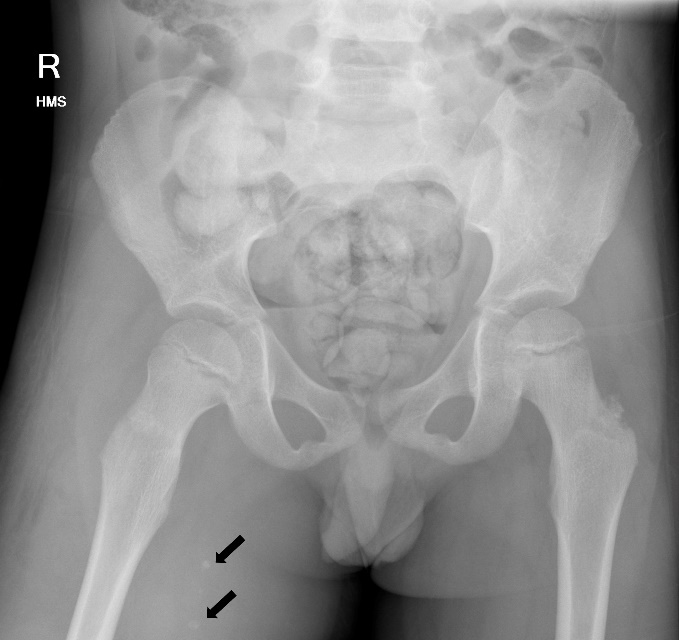

Blood results revealed a high white blood cell count (30.3 × 109/L) with neutrophilia and high C-reactive protein (245.2 mg/L). An X-ray of the hip was performed and interpreted as normal, although in retrospect, phleboliths were present in the region of the adductor muscles (Figure 1). Abdominal CT was normal. Fat stranding, soft tissue swelling and possible fluid collections were identified within the anterior and medial thigh on CT. Retrospectively, there were also multiple intramuscular phleboliths within the adductor muscles (Figure 2).